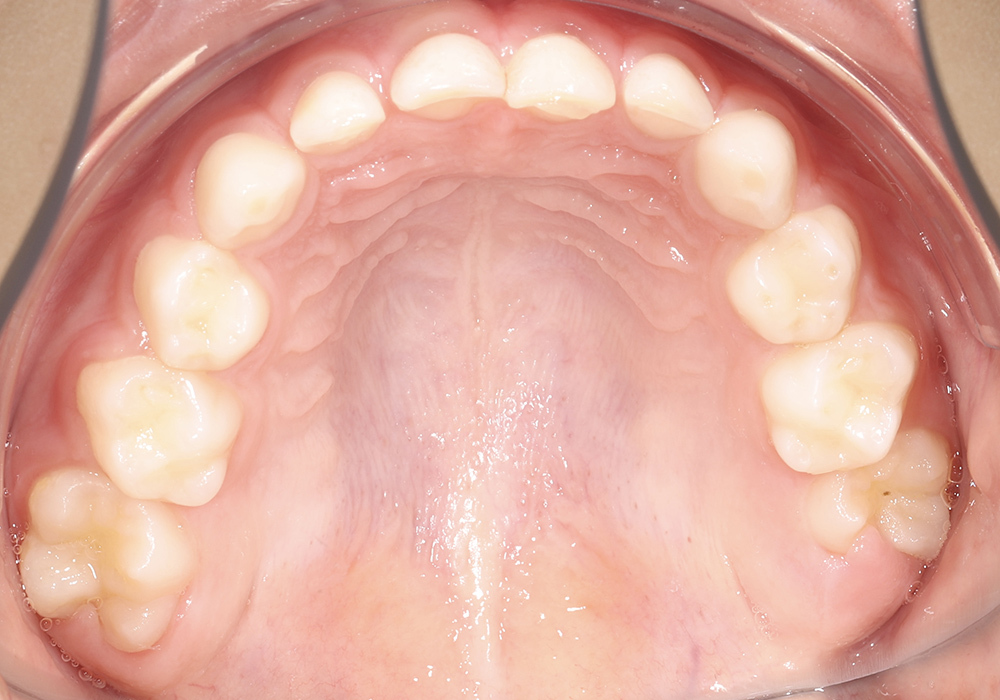

Коррекция прикуса и выравнивание зубных рядов у подростка несъёмной ортодонтической техникой